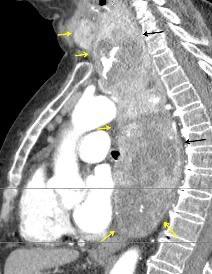

Raro. (2-9% de los T. tímicos). Asintomático. Contiene grasa (hasta 90%) y tejido timico (10-33%). Pueden ser muy grandes y confundirse con cardiomegalia. La tomografía “clásica” muestra los límites de la silueta cardiaca. (flechas)

Líneas paraespinales formando un “paréntesis” por encima del diafragma. El signo señala el origen “intratorácico” de la lesión.

Conrad A et al. Pott’s disease associated with large and multiple abscesses in a 30-year-old migrant from Chad. BMJ Case Rep 2018

(lesiones toracoabdominales) La divergencia de las líneas paraespinales apunta a lesión toracoabdominal, que desde el tórax desciende y penetra en el abdomen.

Signo del “iceberg” positivo en Tb vertebral

Afectación por vía hematógena. Región dorsolumbar más frecuente. Afectación inicial: irregularidad de los platillos vertebrales, disminución del disco intervertebral con esclerosis ósea adyacente. Kim. Radiographics.2001